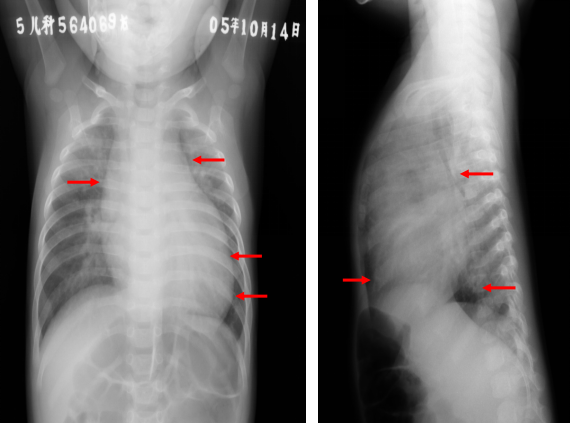

室间隔缺损:胸片表现

◇ 肺血增多

◇ 心胸比例增大:>0.55

◇ 左房、左室增大右室也可增大

◇ 肺动脉段突出

◇ 主动脉结小